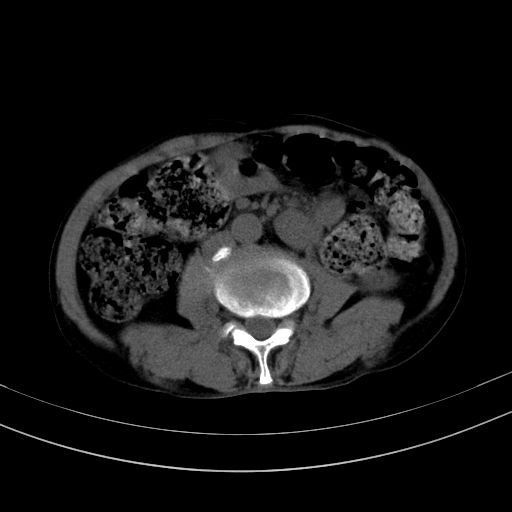

以下是引用37度在2010-1-9 14:37:00的发言:[br]1.双肾囊肿,左肾积水结石,.胆总管轻度扩张;[br]2.病灶在腹膜外,考虑纤维瘤。

以下是引用dyqct在2010-1-9 17:56:00的发言:[br]考虑:1.双肾囊肿,左肾积水结石、旋转不良。[br] 2.右侧腹直肌血肿或纤维瘤。[br]肠道准备不好。做个增强。